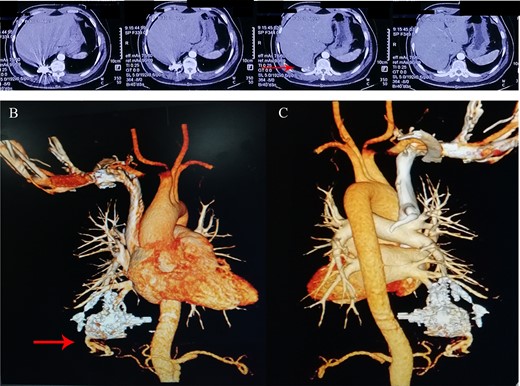

A 44-year-old man presented with hemoptysis and was diagnosed with PAVMs by computed tomography (CT) 3 years ago. In the past 2 years, the patient accepted three times right pulmonary artery branch embolization. But he appeared the same symptom and CT indicated the recurrence of PAVMs only 1 month later after each operation (Fig. 1). Not long after the third intervention, the patient was admitted to the neurology department for paroxysmal numbness and weakness of all limbs and diagnosed as TIA.

(A–C) Chest computer tomography and angiography on three times of pulmonary artery branch embolization.